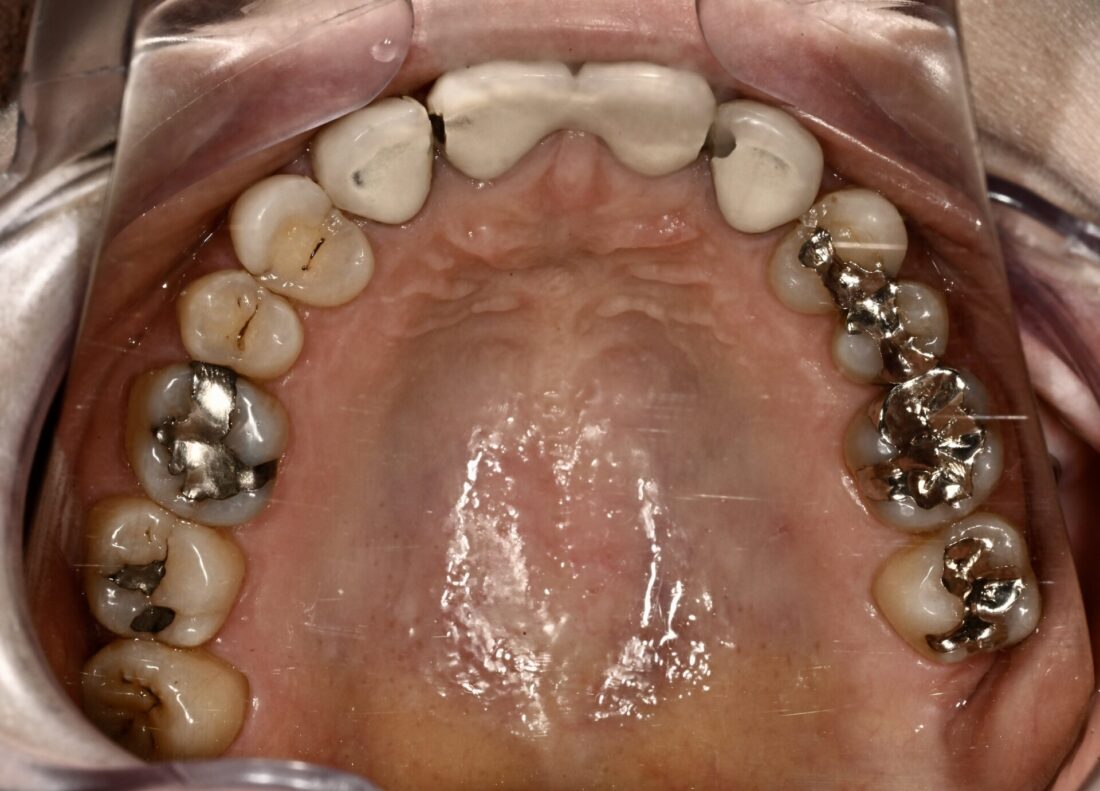

術前

患者さんは元々上顎左右側切歯(2┛┗2)先天的欠如で隙間が開いている状態で、それが気になるということで、「セラミック矯正で有名」な歯科医院を受診、治療されたそうです。最初は隙間が無くなって満足されていた、、、、、というか、まあこんなものか、、、という感じだったらしいです。しかしながらご家族や周囲の方から歯が大きすぎるのではないかとの指摘を多数受け、気になりだしたので当院受診となりました。確かに私が考える「審美」には程遠い状態です。また、処置を始めるにあたり診査、診断を行ったところ他にも歯周病、根管治療、咬合など多数の問題がそのままであり、特に奥歯に関しては保存できない歯牙が多数ありましたが、前医では何の指摘もなかったそうです。現状ならびに治療計画を説明し、臼歯部は保存不可能な歯牙が多数あり、入れ歯もしくはインプラントによる治療が必要なこと、主訴である前歯に関しては矯正治療を組み入れないと審美的結果は得られないことを説明しました。

結局、全顎的治療=包括診療行うことに同意を得ました。

矯正治療は主にアライナーで行いました。